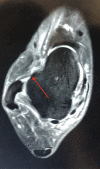

Pic 02: 3D MRI Sequence: Untreated Images

Further, we go for second opinion it is better in can of illusive ligament tears. However take a look at ligament tear seen in above images (Pic 01.02 and 03). They are copied from the paper submitted by Yan Xu to PMC. The order of images shows up clarity of the tear with better perspective. It might be good to have elementary 2D or 3D sequences but its very good to mimic the images in Isometric form. That is to create the 3D Models out of these 2D or 3D MRI Images. It takes involvement of senior radiologists and efforts to stitch up right images to reconstruct a  proper visual model that shall make sense to the viewer. PMC study indicated contrast between 3D MRI  with 2D MRI in diagnosing ATFL injury. The study took 45 patients with suspected ATFL injury. They were sent to conduct  MRI 2D and also taken 3D MRI sequences. The position was much made clear with extra efforts. Subsequently,  radiologist were asked  to  reconstruct ot to make 3D model of the body part. To test how accurate the result were, arthroscopic images from surgery were also checked.